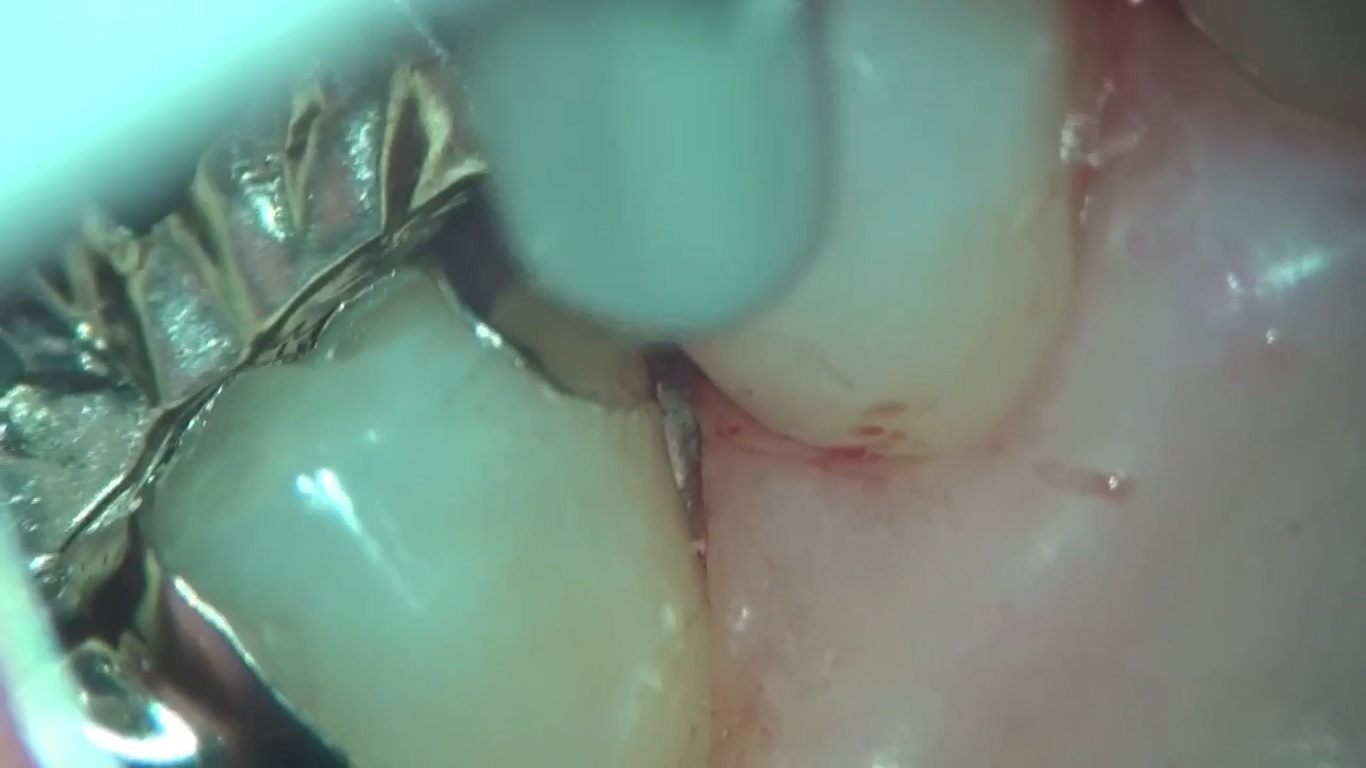

セラミック矯正

審美歯科治療 セラミック

こんにちは。 南館歯科クリニック 院長の木村です。 左下臼歯部の2次虫歯をセラミックで治療したケースです。 この方は、インビザラインで歯列矯正を行った後の虫歯治療です。 矯正で歯を並べる…